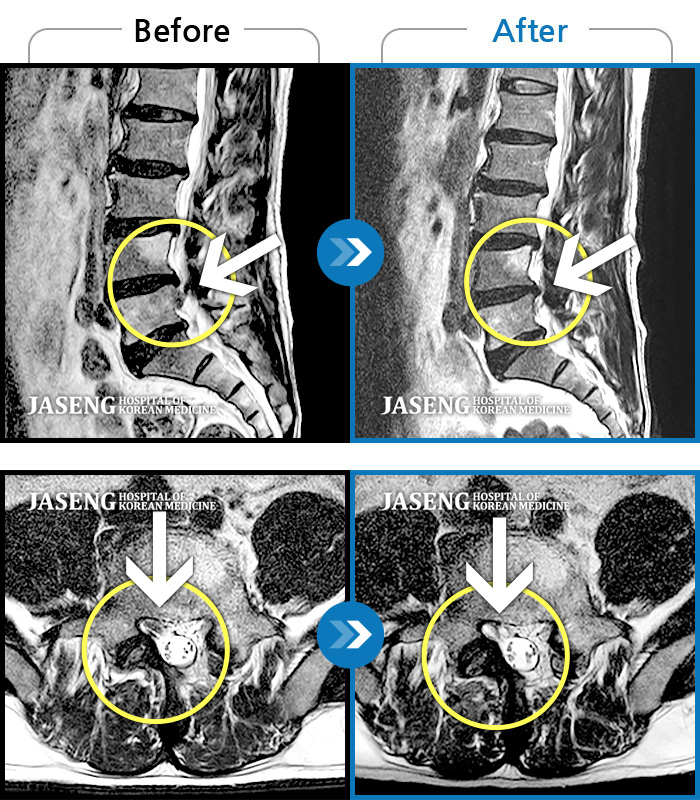

허리디스크

천안 · 윤영웅 원장

허리와 좌측 다리 통증, 저림이 심해요.

촬영시기

2021.10.25 ~ 2022.05.21

2022.05.24